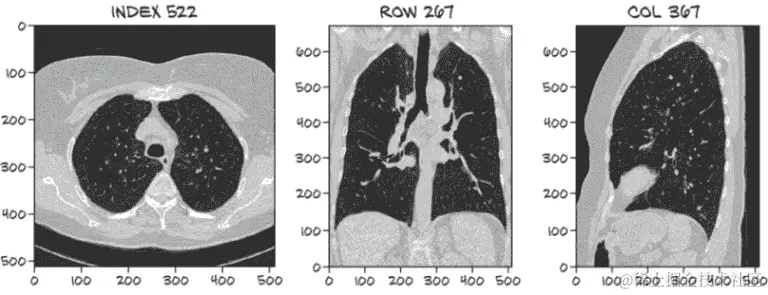

你能够在图 9.5 的三个视图中识别被标记为结节的白点吗?²

如果你需要提示,索引、行和列值可以帮助找到相关的密集组织块。你认为只有这些图像(这意味着只有图像--没有索引、行和列信息!)你能找出肿瘤的相关特性吗?如果你被给予整个 3D 扫描,而不仅仅是与扫描的有趣部分相交的三个切片呢?

注意 如果你找不到肿瘤,不要担心!我们试图说明这些数据有多微妙--难以在视觉上识别是这个例子的全部意义。

图 9.5 一张 CT 扫描,大约有 1,000 个对于未经训练的眼睛看起来像肿瘤的结构。当由人类专家审查时,只有一个被确定为结节。其余的是正常的解剖结构,如血管、病变和其他无问题的肿块。